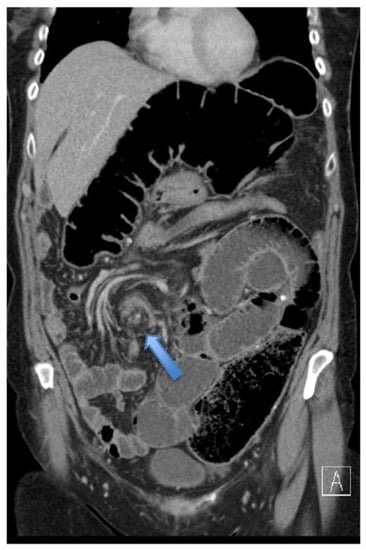

4.4.2. Computerised Tomography (CT) Scan

| CT Abdomen and pelvis | 15 | One patient operated without CT. |

| CV not described | 1 | |

| CV correctly identified | 14 (93.3%) | |

| Caecal diameter >10 cm | 10 (67%) | |

| Whirl sign | 12 (80%) | |

| Split-wall sign | 13 (86.6%) | |

| X-marks-the-spot sign | 14 (93.3%) | |

| Double transition point | 13 (86.6%) | |

| Ileocaecal twist | 13 (86.6%) | |

| Central appendix | 11 (73.3%) |